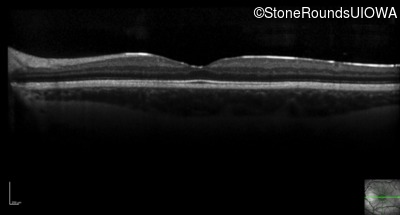

Optical Coherence Tomography - Left - 20/40

Exemplar / OCT Stack